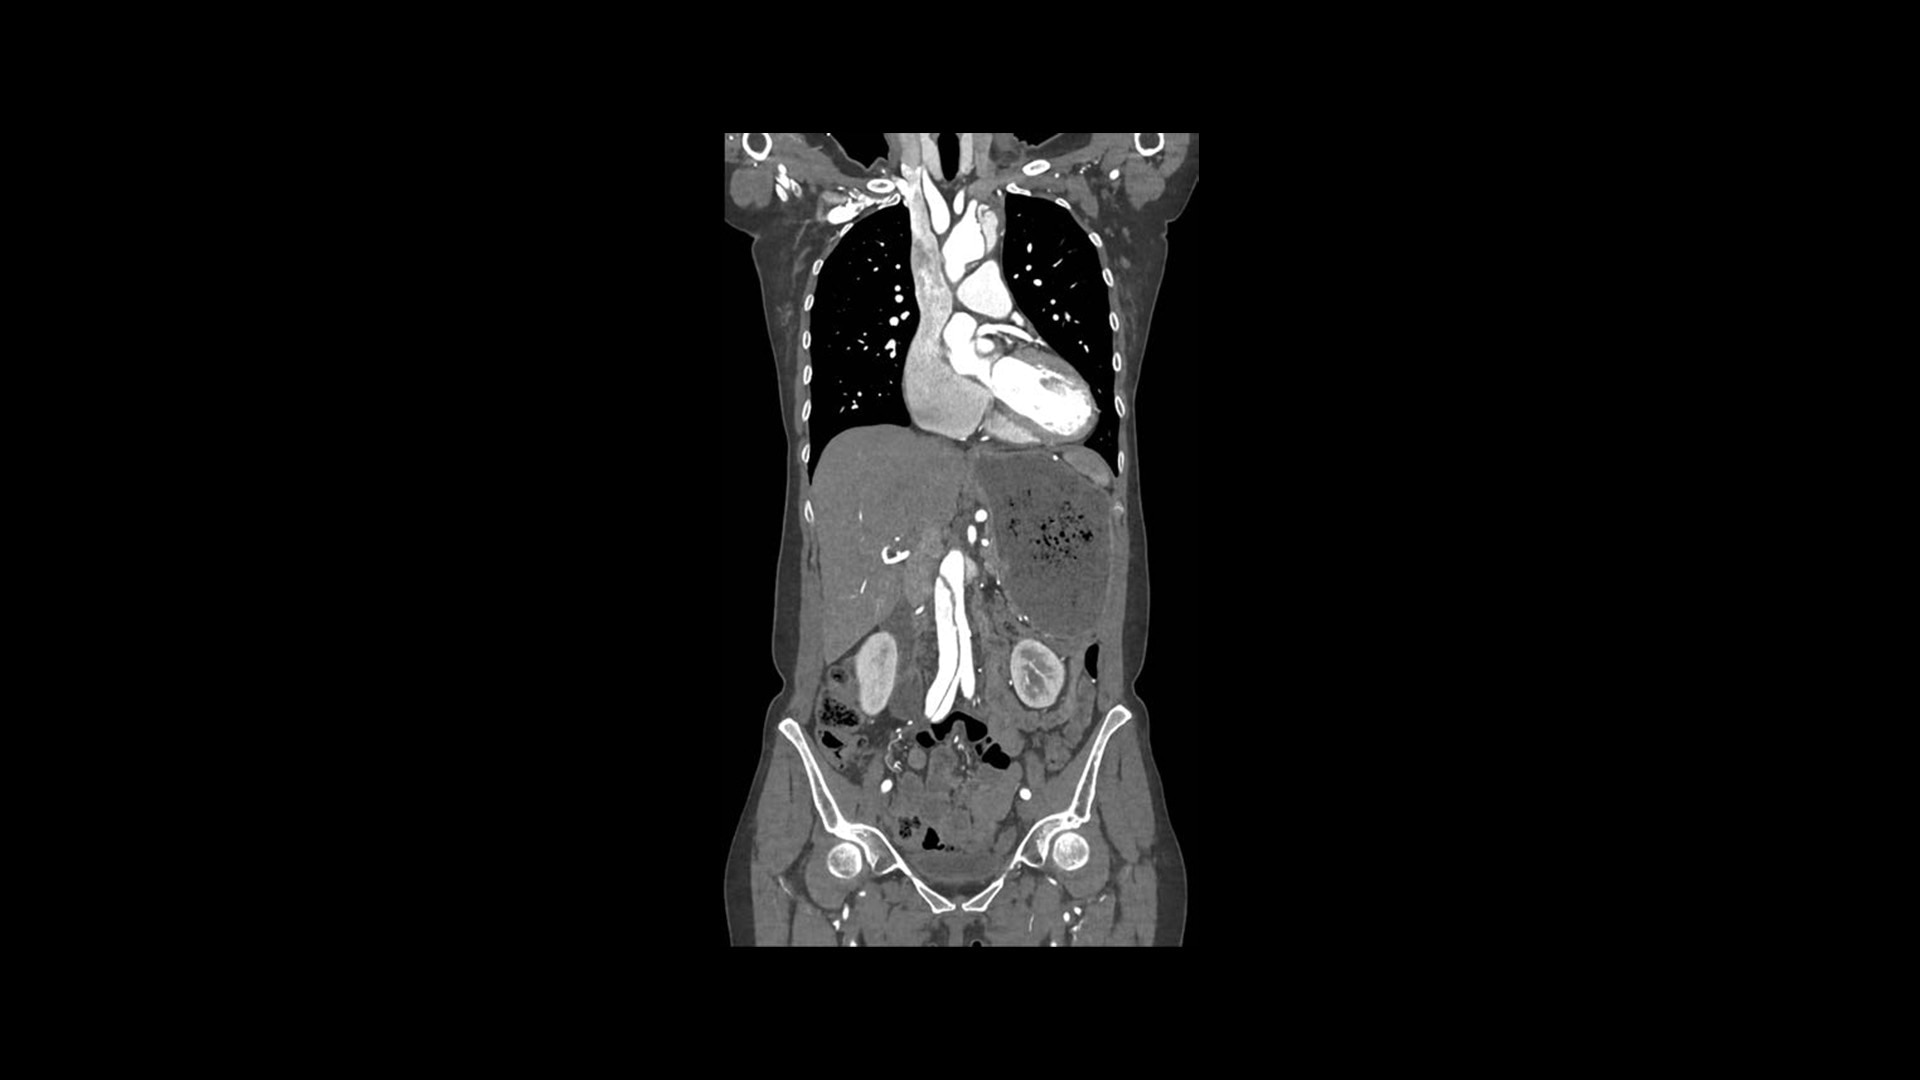

True Enhance DL

Designed to enhance what matters

True Enhance DL is a deep learning-based processing method intended for contrast enhancement of single energy images. True Enhance DL uses a dedicated Deep Neural Network (DNN) trained to estimate monochromatic, 50 keV GSI images from single-energy X-ray. This technology brings four deep learning models that the user can choose depending on different contrast enhancement phases by clinical tasks.